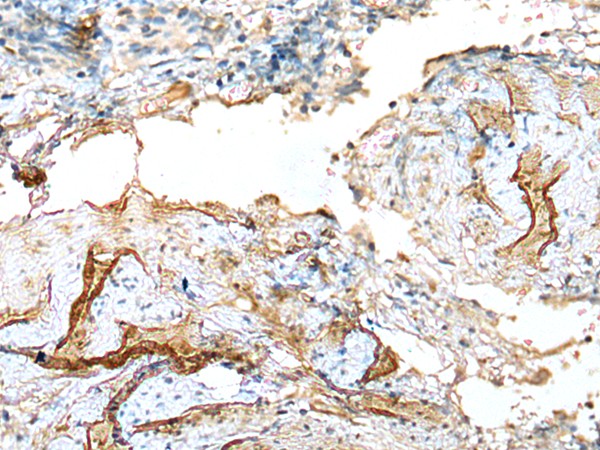

兔抗LDHD多克隆抗体

酶联免疫吸附测定(ELISA),免疫组织化学(IHC)